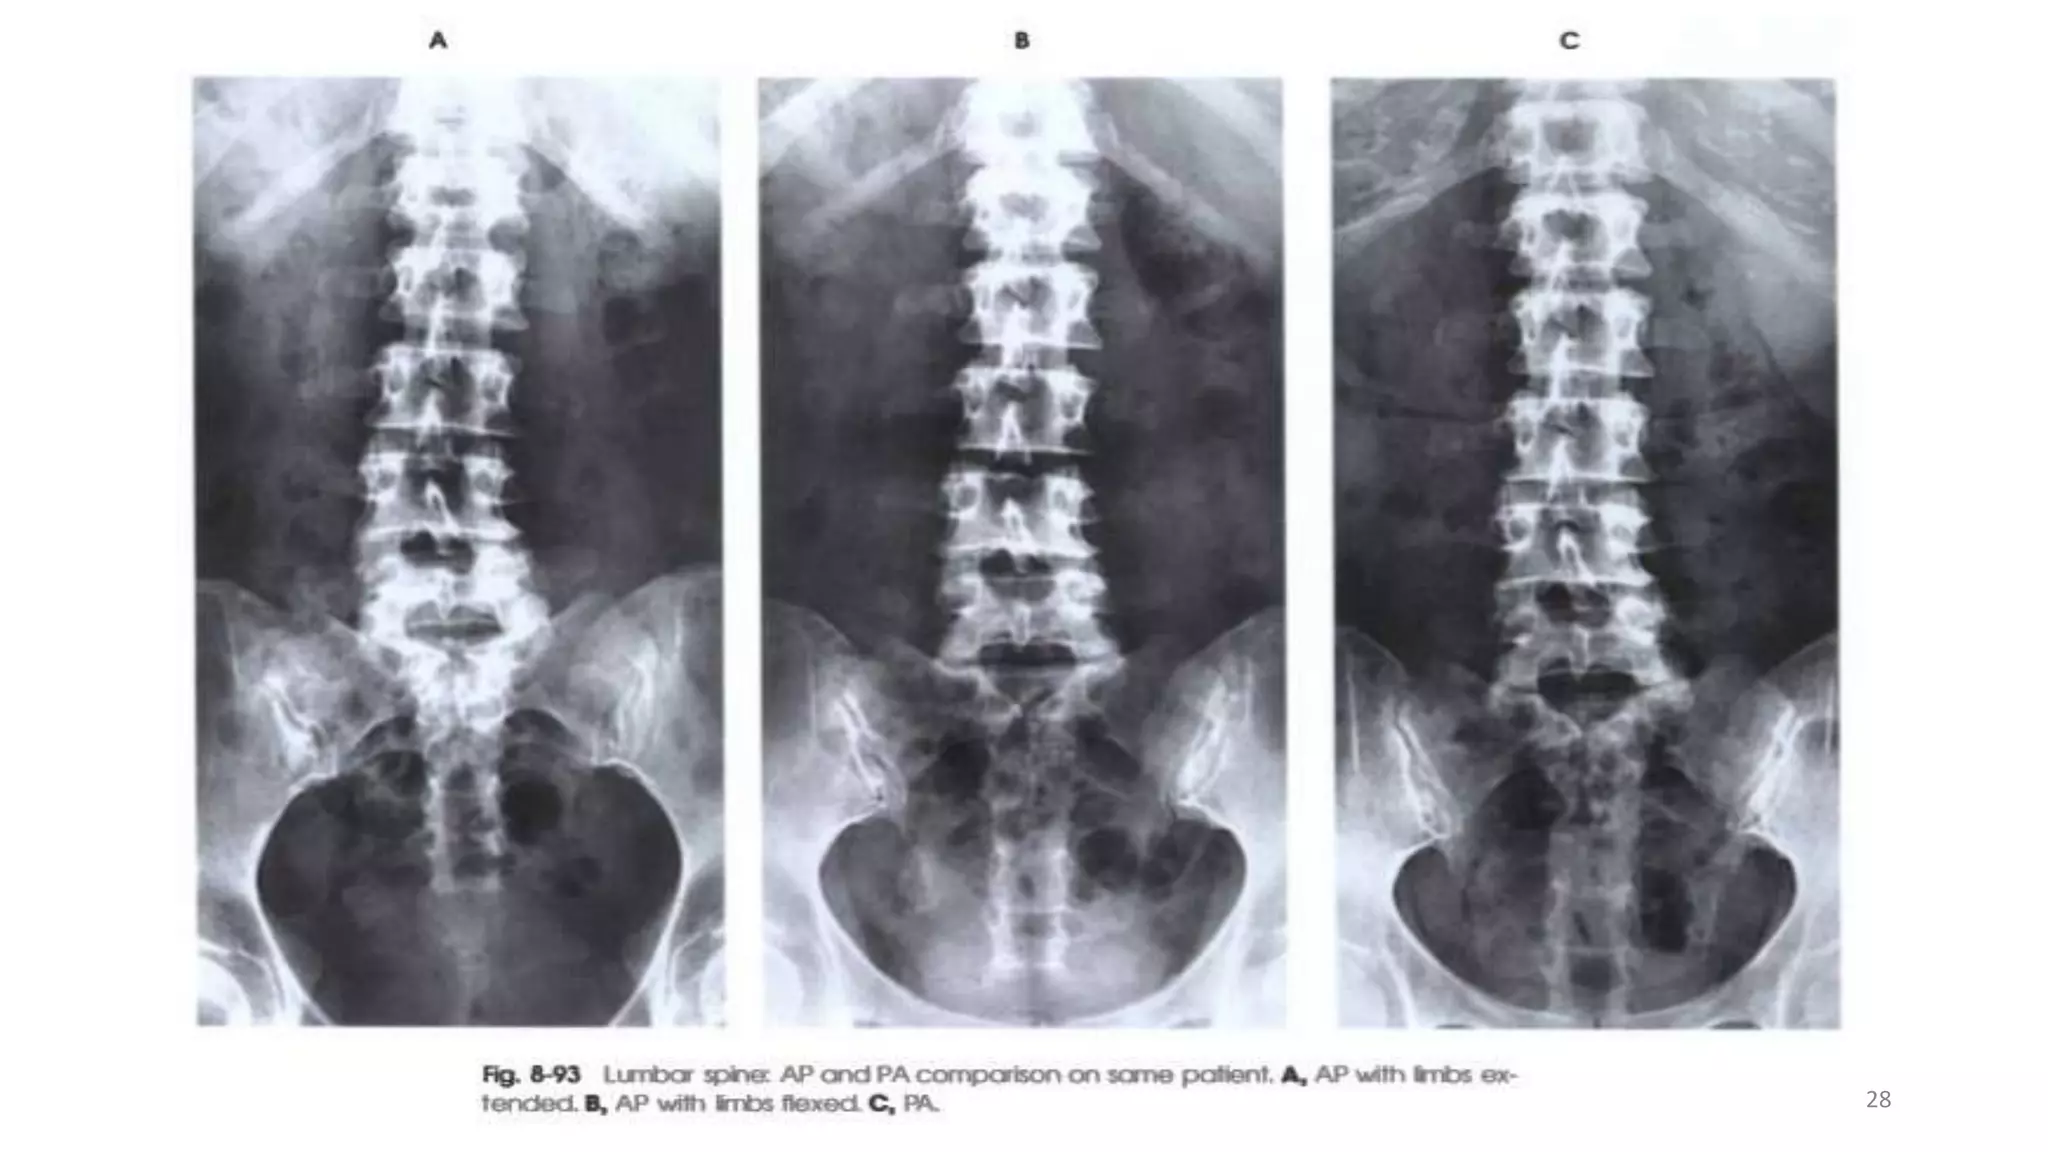

28

ESSIANTAL IMAGE CRITERIA Theimage should include from the (T12)down, to include all of the Sacro-iliac joint. Rotation can be assessed by ensuring that the Sacro- iliac joints are the equidistant from the spine. The exposure used should produce a density such that bony detail can be discerned throughout the region of interest. 27

• 28.